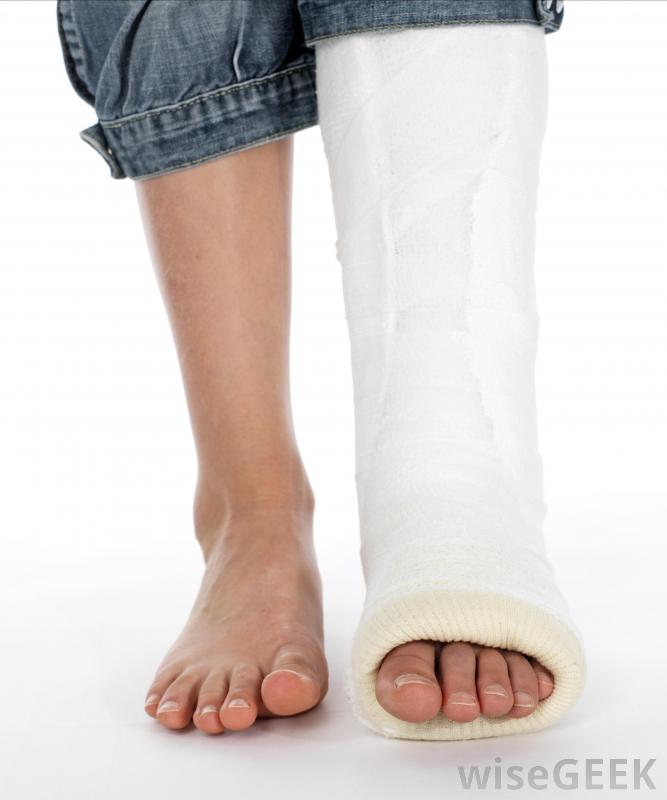

腓骨手術治療腓骨骨折或缺損,小腿骨,或獲取移植材料。手術的具體細節取決于患者為什么需要手術。可能由足踝專家、骨科醫生進行,或者是神經外科醫生。康復時間從幾個小時到幾周或幾個月不等,通過物理療法來重建患肢的力量。如果患者想了解更多關于治療方案和醫生建議的信息,他們可以在手術前向其他外科醫生尋求第二意見腓骨是小腿中較薄的長骨,需要進行腓骨手術的一個常見原因是修復骨折沿著小腿外側延伸至腳踝,通常在踝關節附近骨折。有些骨折可以通過石膏固定修復,但其他骨折可能需要手術治療。這包括在骨骼編織時用釘住骨頭使其穩定,以及檢查韌帶、肌腱的損傷,這種損傷可以在腓骨手術中得到糾正。腓骨手術后,腿通常被固定在石膏中另一個可能出現在腓骨周圍的問題是神經卡壓,這可能導致刺痛感、疼痛或無法控制腳神經外科醫生可能會建議腓骨手術來釋放被困的神經并重新定位,這樣患者就不太可能再次出現這種問題。其他的手術可以解決諸如:受傷后腓骨周圍韌帶撕裂;骨骼形狀異常;或關節炎和感染引起的損傷修復骨折是進行腓骨手術的最常見原因腓骨植入身體其他部位。在骨移植手術中,病人被麻醉,同時采集材料樣本并植入新的位置,如頜骨。這可以在嚴重損傷后重建骨骼,或者作為矯正手術的一部分來解決先天性畸形。在這種情況下,手術團隊可能會包括重建外科醫生來創造一個平滑而均勻的外觀。手術所需的麻醉水平可能會有所不同。對一些人來說,只有清醒鎮靜和局部麻醉劑是必需的。其他人需要全身麻醉以確保病人的安全,這通常會導致較長時間的恢復。患者應在腓骨手術后盡快進行活動,以降低血栓的風險,并開始重建腿部的力量。建議他們考慮將物理治療作為恢復的一部分腓骨手術對于修復腓骨(小腿的一塊骨頭)的骨折或缺損是必要的。